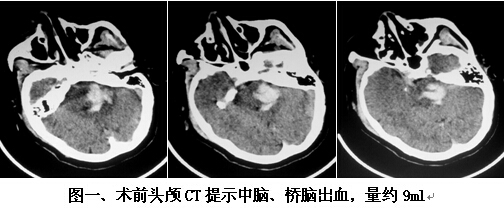

患者男,63歲,因突發(fā)神志不清2小時入院。入院時神志呈淺昏迷狀,頭顱CT提示腦干出血(橋腦、中腦區(qū)域,量約9ml)(見圖一)。神經(jīng)外科鐘三寶主任醫(yī)師查看患者后,分析患者病史、臨床表現(xiàn)及體查,結合影像學結果,考慮患者為重癥高血壓性腦干出血,需開顱行腦干血腫清除術。在發(fā)病后6小時左右,由鐘三寶主任醫(yī)師主刀,帶領李遠志副主任醫(yī)師為患者進行了手術。根據(jù)Brown兩點定位法則,采取枕下乙狀竇后入路,手術頭皮切口設計為勾型,骨窗大小約3cm*4cm(見圖二),術中清除腦干血腫約10ml,手術非常成功。術后復查頭顱CT提示腦干血腫基本清除(見圖三)。